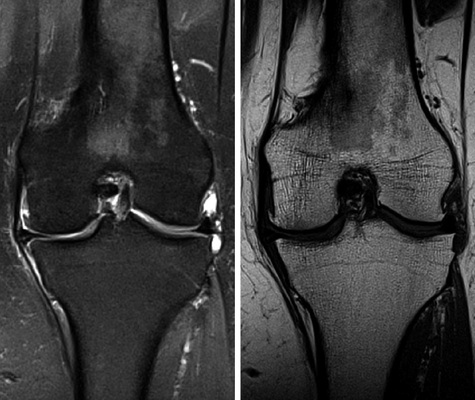

Die MRT erfasst im Gegensatz zu der Röntgendiagnostik begleitende Kniebinnenveränderungen der Menisken, Bänder und des Knochen-marks und bietet dem Betrachter ein umfassendes Bild über das gesamte Ausmaß der Degeneration (  Abb. 9 ).

Zudem ermöglicht es die Darstellung von Knochenmarködem, das in keiner anderen bildgebenden Technik dargestellt werden kann.